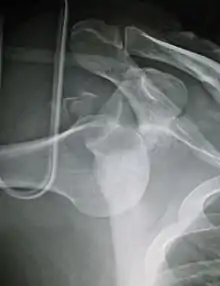

An inferior dislocation of the shoulder after an automobile accident. Note how the humerus is abducted. Also present is a fracture of the greater tuberosity.

Inferior dislocation is the least likely, occurring in less than 1%. This condition is also called luxatio erecta because the arm appears to be permanently held upward or behind the head.[15] It is caused by a hyper abduction of the arm that forces the humeral head against the acromion.[16] Such injuries have a high complication rate as many vascular, neurological, tendon, and ligament injuries are likely to occur from this mechanism of injury.